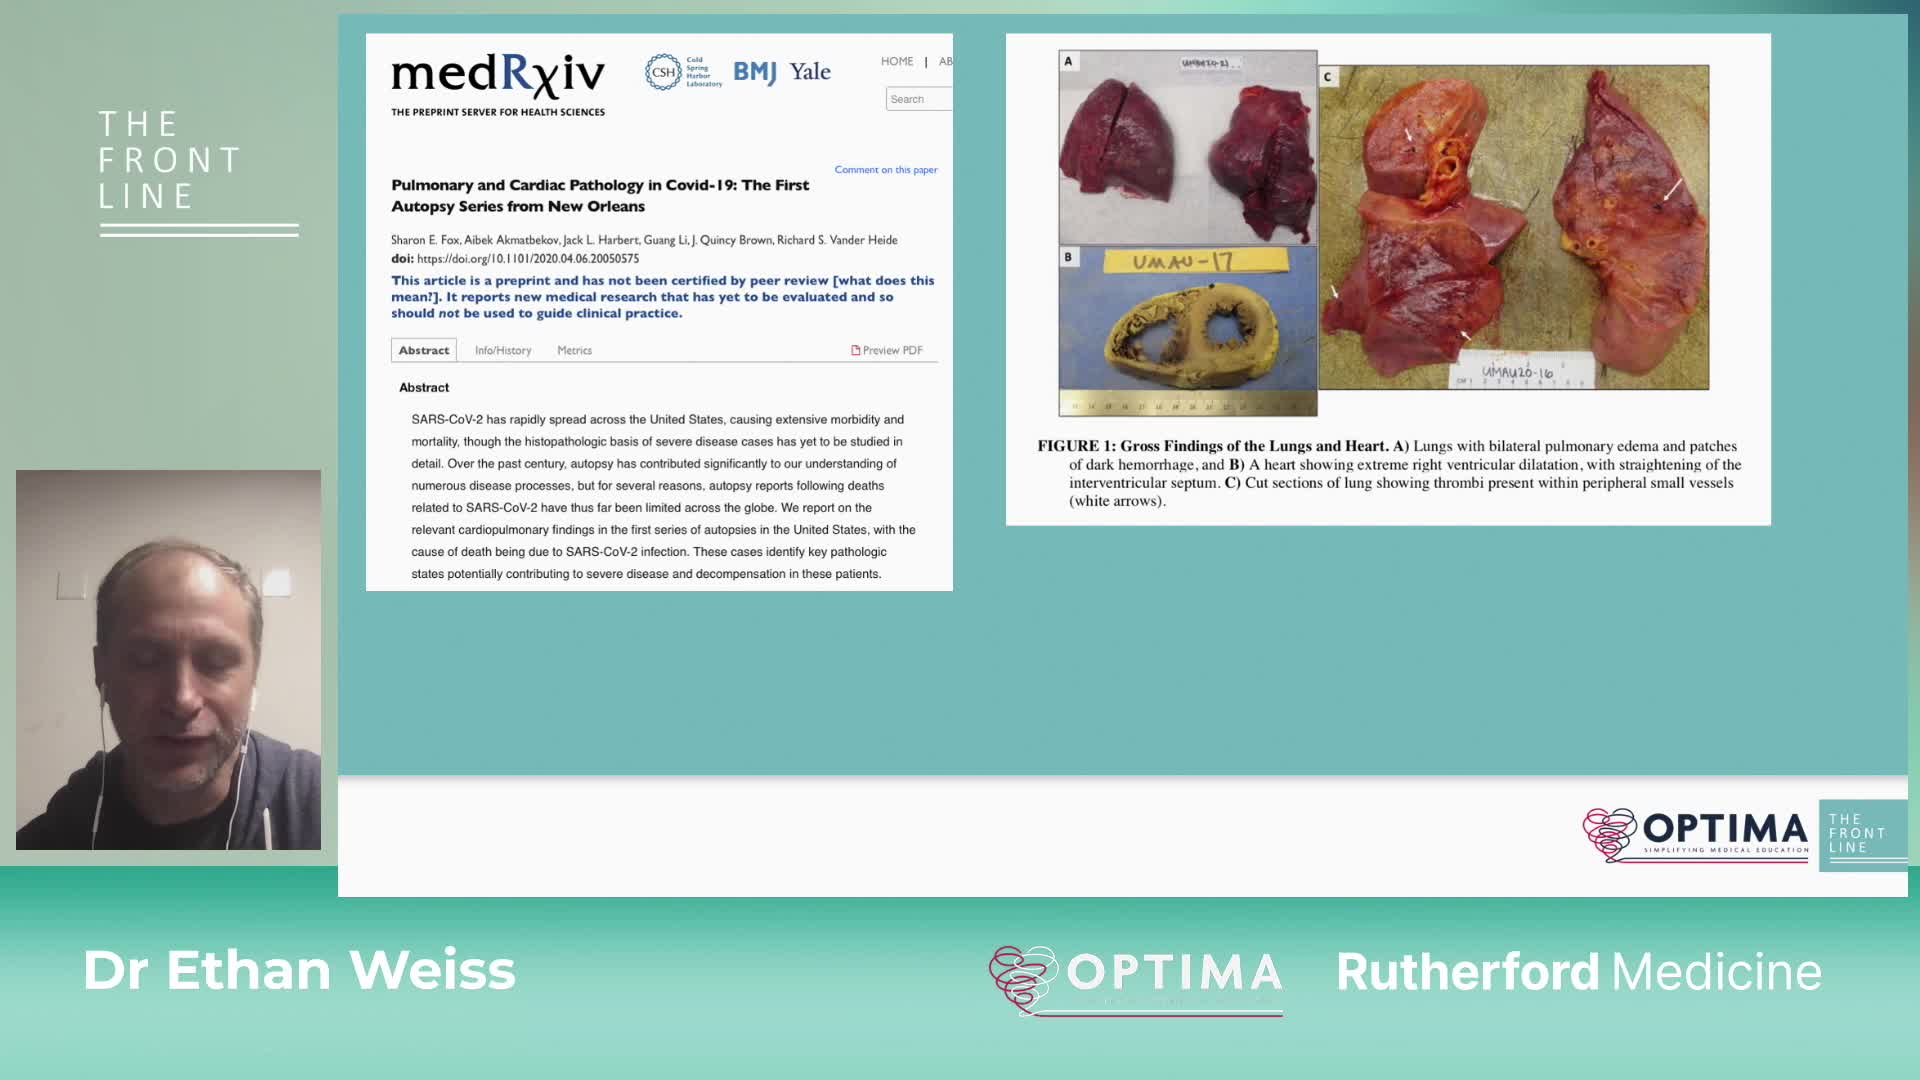

COVID-19: The Front Line. The potential role of anti-thrombotic therapy in COVID-19